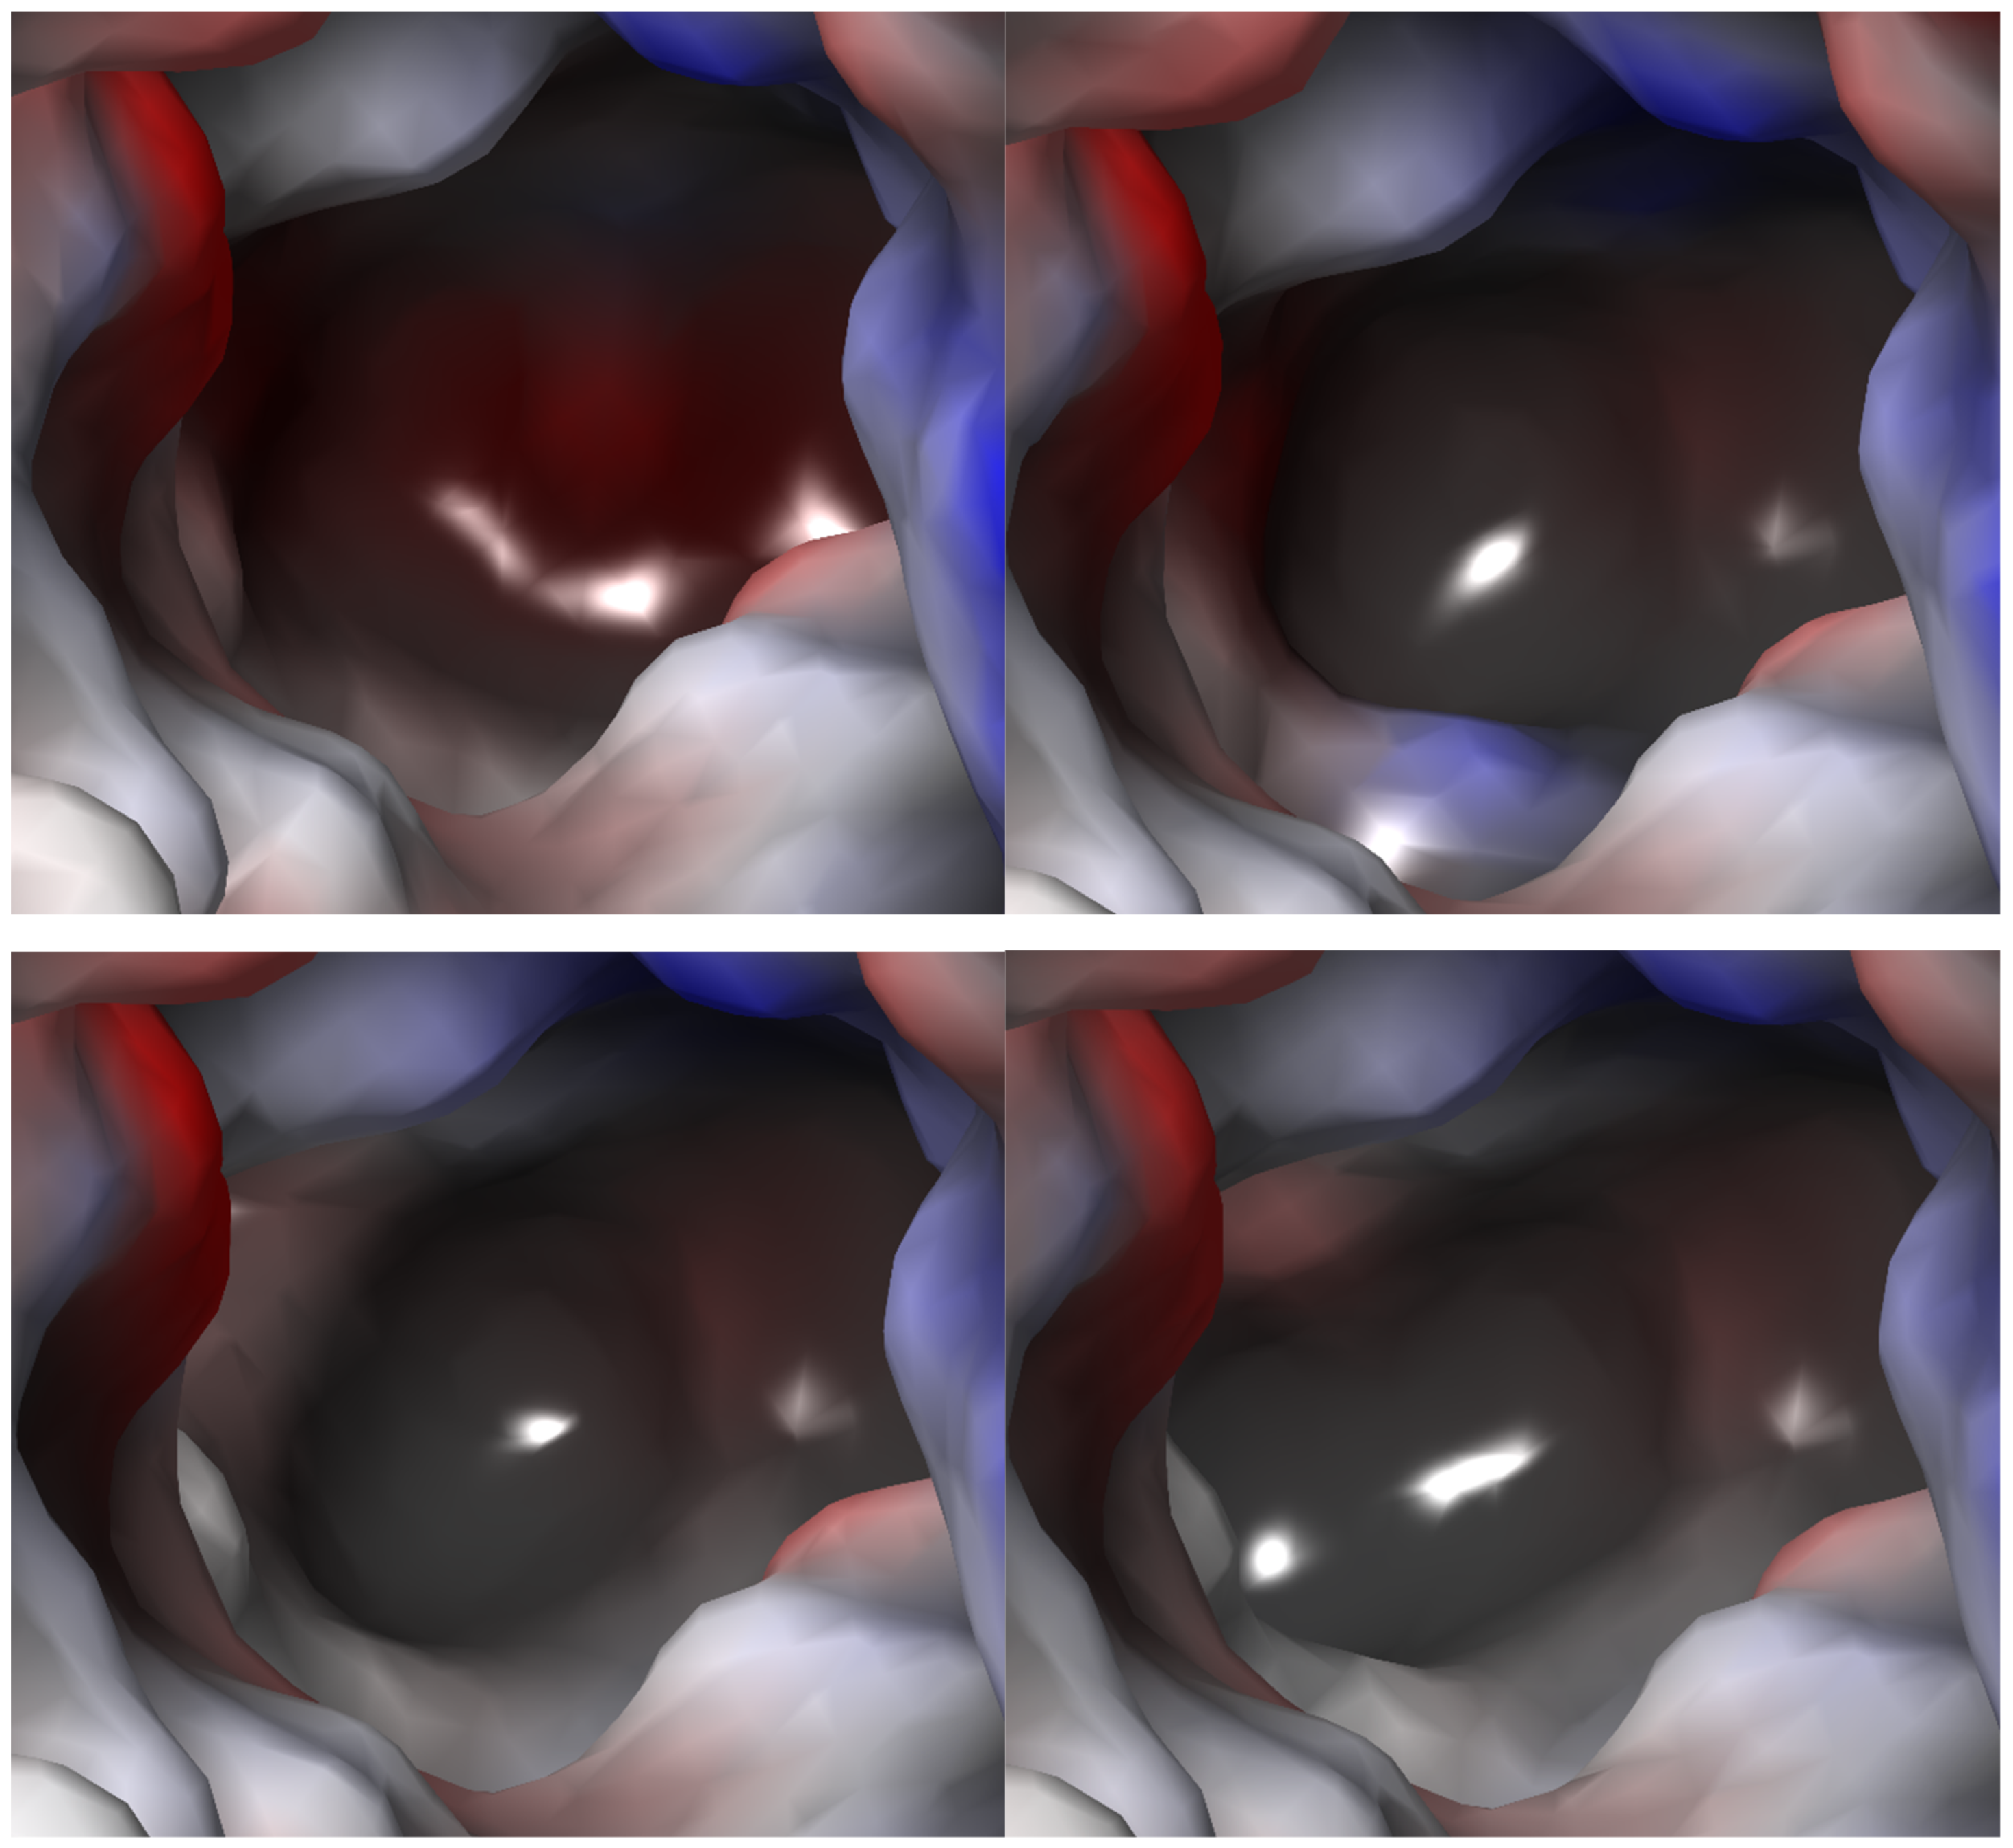

2.2.3. Binding Sites

2.2.4. S1 Binding Site Analysis

2.3. TauT Docking Studies

2.3.1. TauT Ligands Binding Mode